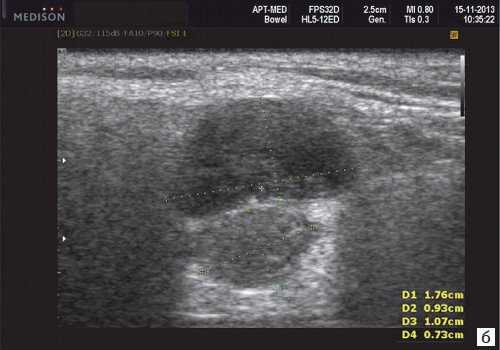

В отечественной и зарубежной литературе встречается много работ, посвященных сиалогии (от греч. Sialon - слюна и logos - учение) - науке о заболеваниях и повреждениях слюнных желез, методах их диагностики и лечения. По данным разных авторов, на долю заболеваний слюнных желез приходится до 24% всей стоматологической патологии. В настоящее время в клинической практике наиболее часто встречаются дистрофические, воспалительные заболевания слюнных желез (сиалоаденозы, сиалоадениты), а также опухоли и врожденные пороки развития слюнных желез. Кроме того, патологические изменения слюнных желез часто сопутствуют другим заболеваниям (сахарный диабет, бронхоэктатическая болезнь, саркоидоз, цирроз печени, гипертриглицеридемия, лимфогранулематоз и др.).

- ультразвуковой метод (является наиболее доступным, безопасным и информативным в процессе дифференциальной диагностики патологического состояния слюнных желез).

- обструктивные сиаладениты, развивающиеся при затруднении оттока слюны при обструкции выводного протока камнем (рис. 5-7) или сгустившимся секретом, а также вследствие рубцового стеноза протока. По распространенности процесса различают очаговый, диффузный сиаладениты и сиалодохит - воспаление выводного протока. Течение процесса может быть острым и хроническим;

Рис. 5. Камень протока поднижнечелюстной слюнной железы.

Рис. 6. Камень в паренхиме поднижнечелюстной слюнной железы.

Рис. 7. Камень в протоке поднижнечелюстной слюнной железы.